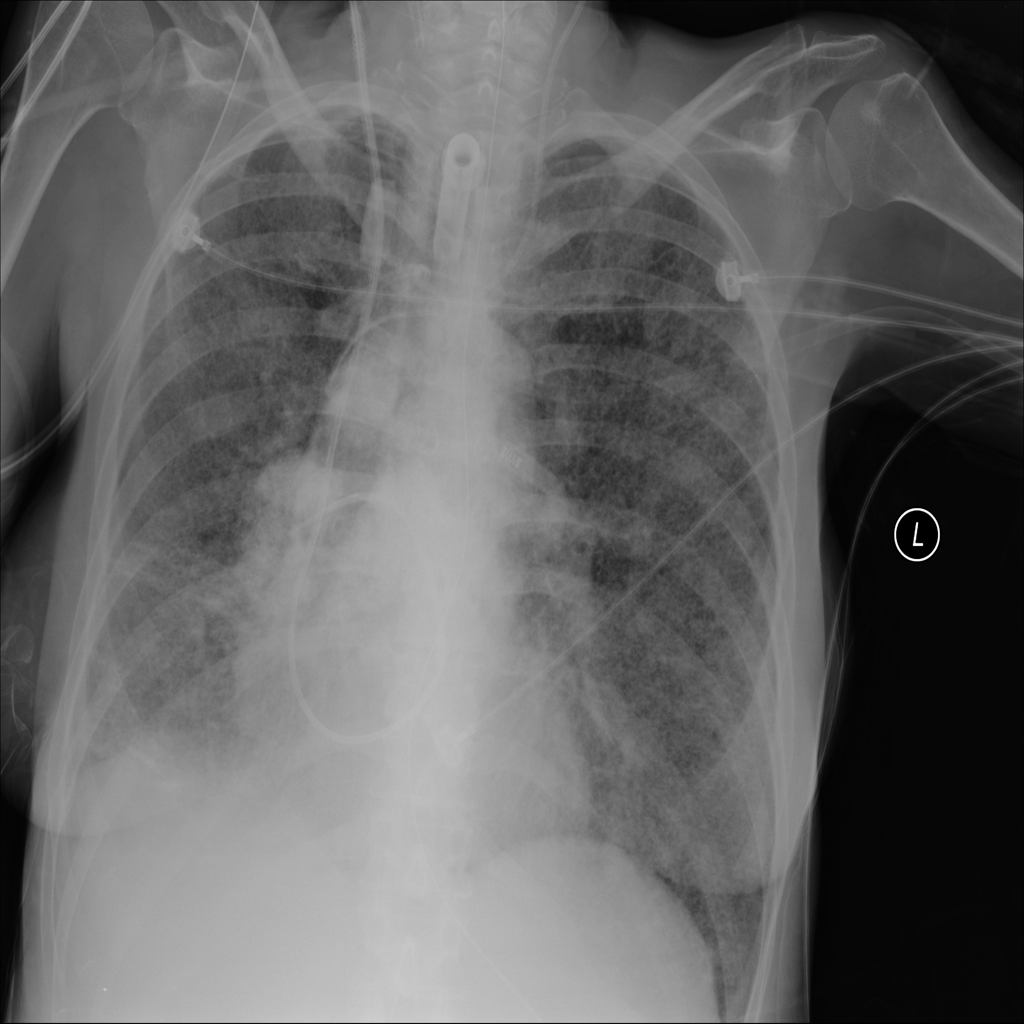

Consolidation

Consolidation refers to air-space filling that makes part of the lung appear denser on imaging.

Showing up to 90 reference images for Consolidation.

PAT-C1A7 · IMG-055Consolidation

PAT-C1A7 · IMG-055

AP